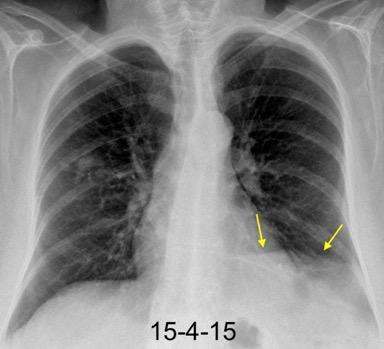

37. ESPLENOSIS TORÁCICA

Autotrasplante de tejido esplénico al tórax tras trauma. (T. Penetrante más frecuente que cerrado)

Causas:

1. Trauma 2.Esplenectomía

3. Diseminación hematógena

4. ¿Hipoxia?

T1: Hipointenso

T2: Hiperintenso. Puede ser hipointenso. (Hierro)

Esplenectomía previa

Ferrer TM et al. Thoracic splenosis: History is the key. Respiratory Medicine Case Reports. 2017